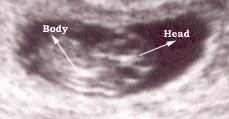

Photo Three

12 weeks fetus

This is a twelve weeks pregnancy as seen by external (through the abdomen) sonar.